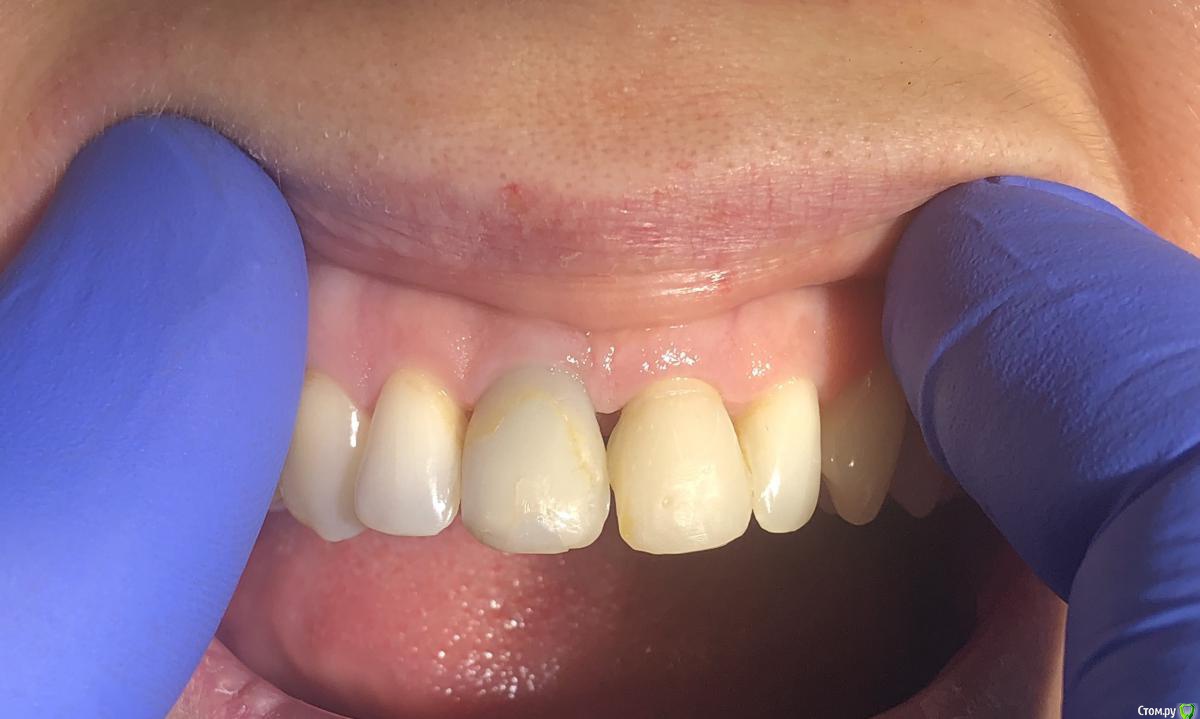

Александр07 Опубликовано 2 мая, 2020 Поделиться Опубликовано 2 мая, 2020 Коллеги доброго дня Обратилась молодая пациентка , в районе 30, десневая улыбка, планируется пластика во фронте с целью увеличения высоты сосочков, ну и объём можно немного добавить1.1 импл, сосочек 2.1-2.2 тоже ушёл от предыдущих операций, Раздумываю какой метод выбрать, есть несколько вариантовСклоняюсь к методу по Цуру - создание туннеля и подтянуть транс швами за межзубные контакты Вторым вариантом методика Сузуки но объём тогда вестибулярно не затронемИ по Зукелли , но опасаюсь осложнений в виде рубцов и т д, Кто что посоветует) Ссылка на комментарий

kramer Опубликовано 2 мая, 2020 Поделиться Опубликовано 2 мая, 2020 Сделал бы более протяженный контакт между 11 и 21 Ссылка на комментарий

Aquarius Опубликовано 2 мая, 2020 Поделиться Опубликовано 2 мая, 2020 (изменено) Я за Масану. И контакт на 21 надо изменить Изменено 2 мая, 2020 пользователем Aquarius Ссылка на комментарий

krokomot Опубликовано 2 мая, 2020 Поделиться Опубликовано 2 мая, 2020 нужна другая форма коронок, может и пластика не потребуется 2 Ссылка на комментарий

krokomot Опубликовано 2 мая, 2020 Поделиться Опубликовано 2 мая, 2020 проблема центрального сосочка в коронке 2.1. нудно переделать коронку 2.1 и 1.1, потом думать о пластиках. Ссылка на комментарий

Irouil Опубликовано 2 мая, 2020 Поделиться Опубликовано 2 мая, 2020 Я тоже не вижу, что тут еще давить. У коронки плохой контур в пришеечной части, но ближе к платформе винта коронка должна быть тоньше с таким рентгеном, значит там поддержка тканей еще уменьшится. Судя по оклюзионному снимку в оро-вестибулярном направлении коронке не хватает объёма, зенит тоже апикальнее необходимого. Надо разобраться с соседней 1-кой, если замена там коронки - вариант, то можно рассмотреть апикализацию зенита на зубе на 1 мм в итоге. Но, имхо, без хирургии тут не выйдет ничего Ссылка на комментарий